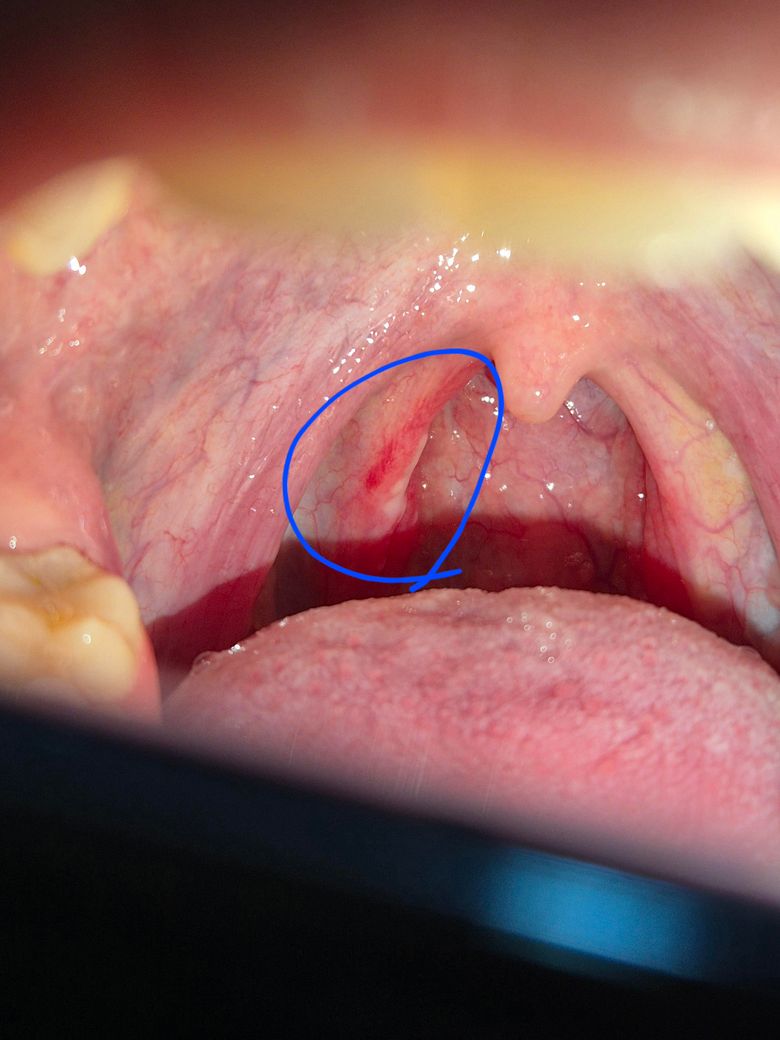

사진상 편도쪽인거같긴한데 삼킬때마다 통증이 있었거든요.. 5월 7일경부터 생긴거같은데 사진상 동그라미 해둔 저 하얀게 뭔지 궁금합니다.. 염증인건가요?

해당 부위는 편도와 연구개(입천장 뒤쪽) 경계 쪽이며, 그 하얀 점은 편도결석(편도석) 또는 표재성 농(고름)일 가능성이 높습니다. 편도염 초기에는 이처럼 하얀 찌꺼기처럼 보이는 삼출물(염증 분비물)이 생길 수 있고, 삼킬 때 통증이 있는 것도 급성 편도염이나 인두염에서 흔히 나타나는 증상입니다.

편도결석은 보통 냄새나는 덩어리로, 음식 찌꺼기와 박테리아가 뭉쳐 생기며 큰 문제가 되진 않지만 반복적으로 생기면 통증과 불편감을 유발할 수 있어요

하지만 지금처럼 삼킴 통증이 며칠째 지속되고 있다면, 바이러스성 혹은 세균성 편도염일 수 있으므로 항생제 치료가 필요한 경우로 보여요. 지금 이비인후과 진료를 권하고 고열, 전신 쇠약감, 통증이 심해지는 경우엔 꼭 이비인후과 진료를 보시길 권합니다.